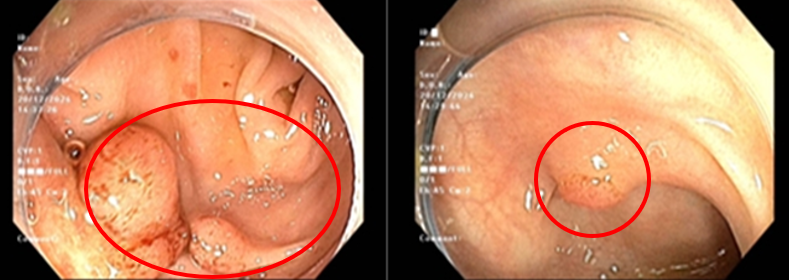

Cách vào viện 1 tháng, bệnh nhân xuất hiện đau tức vùng thượng vị, đau âm ỉ, không lan, đau tăng khi đói, kèm them ợ hơi, ợ chua, không nôn, không buồn nôn, đại tiểu tiện bình thường. Bệnh nhân đi khám được nội soi dạ dày thấy hình ảnh mặt sau hang vị có khối tổn thương nổi gồ kích thước khoảng 0.8cm, sinh thiết cho kết quả viêm teo niêm mạc dạ dày mạn tính hoạt động nhẹ, dị sản ruột, loạn sản độ thấp, Helicobacter Pylori (HP) âm tính. Nội soi đại tràng thấy 4 polyp, kích thước lớn nhất khoảng 1,5cm và có tổn thương dạng lõm kích thước khoảng 1,2cm. Bệnh nhân được cắt polyp cho kết quả giải phẫu bệnh là u tuyến ống, loạn sản độ thấp.

Hình 1: Hình ảnh polyp ở đại tràng

Sau đó bệnh nhân được nội soi cắt hớt dưới niêm mạc (ESD-Endoscopic Submucosal Disection) tổn thương đại tràng cho kết quả giải phẫu bệnh ung thư biểu mô tuyến biệt hóa vừa xâm nhập lớp hạ niêm mạc, diện cắt đáy còn u, diện cắt bên không còn u.

Hình 2: Hình ảnh tổn thương dạng lõm ở đại tràng (a); Cắt hớt dưới niêm mạc tổn thương (b); Tổn thương sau cắt hớt (c); Bệnh phẩm sau cắt hớt (d).